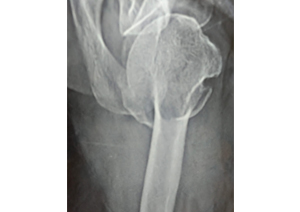

Case:2 Fracture of Neck Humerus with Fracture of Greater Tuberosity

Pre-Op AP

Pre-Op Trausaxillay